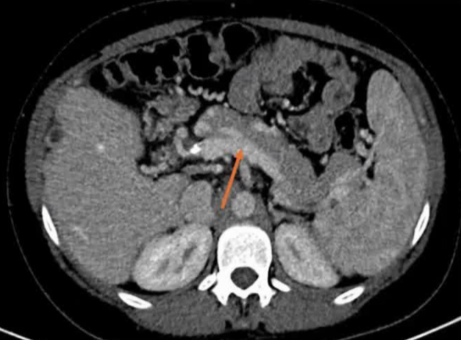

该程序包含以下步骤: 经脾脏入路:在超声引导下,刺穿脾静脉内的一个实质内分支。 在通过脾静脉造影确认了静脉通路后,导管和导丝被推进,以穿过脾静脉并抵达血栓化的门静脉。在门静脉/右门静脉分支处放置圈套器,为TIPS穿刺精准定位。TIPS穿刺圈套器,并穿过圈套器完成TIPS

步骤: 鉴于慢性血栓形成的复杂性: 一种经脾脏途径的门静脉再通术(PVR)。 随后是经颈静脉肝内门体分流术 。

结果:术后影像学检查显示门静脉和脾静脉的血流情况有所改善,且残留血栓极少。